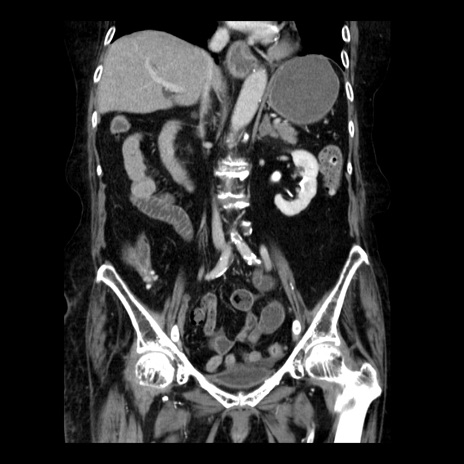

症例14(冠状断像)

【症例】 90歳代女性

【主訴】 腹痛・嘔吐

【現病歴】今朝から左側腹部痛を認めた。 経過観察していたが、嘔吐を認めたため来院。

【既往歴】 子宮癌術後

【身体所見】 意識清明、BP 127/54mmHg、P 98bpm Sp02 95%(RA)、BT 35.8°C、腹部平坦・軟腸ぜん動音聴取良好、右下腹部圧痛(+) 反跳痛なし

【データ】WBC 9800、CRP 0.46